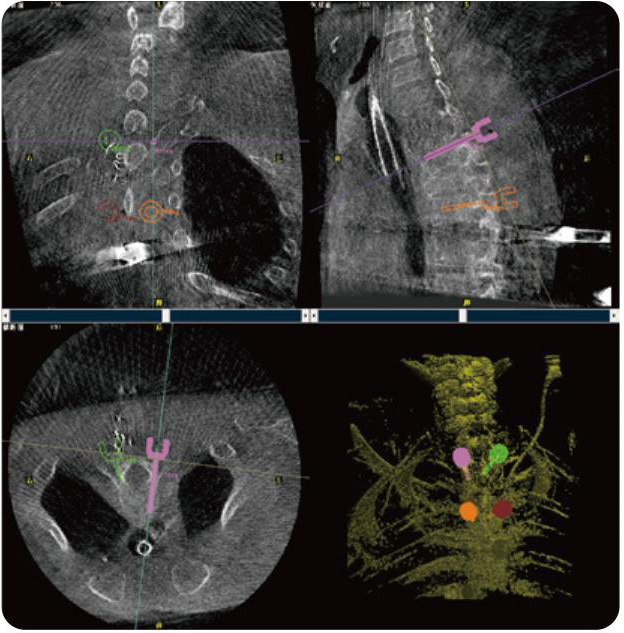

PL300B可應(yīng)用于多節(jié)段脊柱外科手術(shù),輔助醫(yī)生定位病灶部位,為脊柱外科手術(shù)(經(jīng)皮椎體成形術(shù)、椎弓根螺釘內(nèi)固定術(shù)等術(shù)式)提供術(shù)前手術(shù)流程規(guī)劃、入釘位置、角度可視化引導(dǎo),模擬仿真入釘輔助。

PL300B搭配普愛醫(yī)療自主研發(fā)生產(chǎn)的平板3D C形臂,借助一體化自適應(yīng)配準(zhǔn)( 軌跡配準(zhǔn))技術(shù),通過追蹤C(jī)形臂三維采集軌跡,自動完成圖像坐標(biāo)建立和系統(tǒng)坐標(biāo)配準(zhǔn)。配準(zhǔn)精度更高,操作步驟少,系統(tǒng)運(yùn)作效率高。